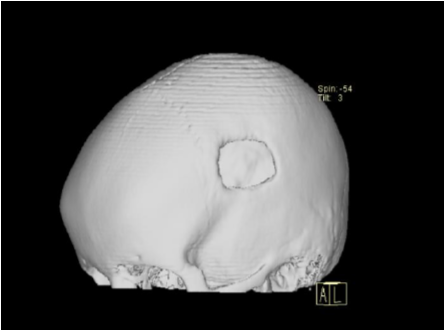

En estudio de Tomografía Computarizada simple de cráneo realizada un mes previo al acto quirúrgico valorada en cortes axiales y coronales se observa en ventana ósea lesión ocupante de espacio (LOE), hipodensa, extradural de forma ovoidea, de característica lítica, ubicada en región parietal izquierda con aproximadamente 8,8x17 mm de diámetro. Ventana parenquimatosa sin alteraciones (Fig. 1a, 1b). En resonancia magnética cerebral contrastada se observa imagen extradural, de forma ovoidea, bien delimitada con bordes regulares de características quísticas en región parietal izquierda, de comportamiento heterogéneo, hipo e isointensa en secuencia T1, hiperintensa en T2 y FLAIR, sin captación tras la administración de contraste endovenoso y restricción en Difusión (Fig. 2). Se realizó reconstrucción 3D postquirúrgica donde se observa defecto óseo en hueso parietal izquierdo (Fig. 3).